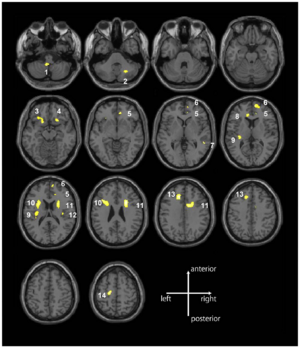

Potential of Diffusion Tensor Imaging and Relaxometry for the Detection of Specific Pathological Alterations in Parkinson's Disease (PD)

Publication: PLoS One. 2015 Dec 29;10(12):e0145493. PMID: 26713760 | PDF Authors: Esterhammer R, Seppi K, Reiter E, Pinter B, Mueller C, Kremser C, Zitzelsberger T, Nocker M, Scherfler C, Poewe W, Schocke M. Institution: Department of Radiology, University Hospital, Innsbruck Medical University, Innsbruck, Austria. Background/Purpose: The purpose of the present study was to evaluate the potential of multimodal MR imaging including mean diffusivity (MD), fractional anisotropy (FA), relaxation rates R2 and R2* to detect disease specific alterations in Parkinson's Disease (PD). We enrolled 82 PD patients (PD-all) with varying disease durations (≤5 years: PD≤5, n = 43; >5 years: PD>5, n = 39) and 38 matched healthy controls (HC), receiving diffusion tensor imaging as well as R2 and R2* relaxometry calculated from multi-echo T2*-weighted and dual-echo TSE imaging, respectively. ROIs were drawn to delineate caudate nucleus (CN), putamen (PU), globus pallidus (GP) and substantia nigra (SN) on the co-registered maps. The SN was divided in 3 descending levels (SL 1-3). The most significant parameters were used for a flexible discrimination analysis (FDA) in a training collective consisting of 25 randomized subjects from each group in order to predict the classification of remaining subjects. PD-all showed significant increases in MD, R2 and R2* within SN and its subregions as well as in MD and R2* within different basal ganglia regions. Compared to the HC group, the PD≤5 and the PD>5 group showed significant MD increases within the SN and its lower two subregions, while the PD≤5 group exhibited significant increases in R2 and R2* within SN and its subregions, and tended to elevation within the basal ganglia. The PD>5 group had significantly increased MD in PU and GP, whereas the PD≤5 group presented normal MD within the basal ganglia. FDA achieved right classification in 84% of study participants. Micro-structural damage affects primarily the SN of PD patients and in later disease stages the basal ganglia. Iron contents of PU, GP and SN are increased at early disease stages of PD. Funding:

The regions-of-interest (ROIs) were manually drawn by an experienced radiologist by using the b 1000 images, averaged for all measured directions, the FA maps and the proton-density weighted images. For that purpose, the maps of ADC, FA, R2 and R2* as well as the proton-density weighted images were first co-registered. The ROIs were segmented by syncing the b 1000 images, averaged for all measured directions, the FA maps and the proton-density weighted images in ImageJ. The ROIs were stored in the ROI manager and transferred to the co-registered maps. The segmented brain regions were highlighted in different colors: CN—black; PU—red; GP—green; TH—white; SN—blue; CC—cyan. The diffusion-weighted images, the R2 and R2*-weighted maps were transferred to the 3D Slicer software in order to co-register the R2 and the R2* maps as well as the MD and the FA maps |